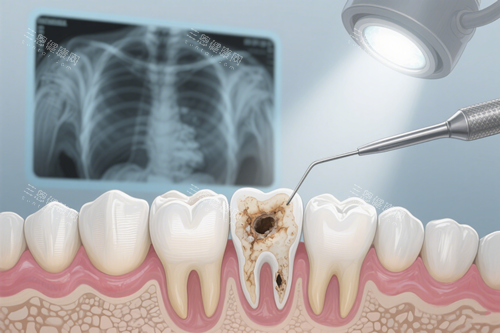

没等两分钟,就被护士领到了诊室。给我看诊的是张医生,戴着眼镜,说话特别亲切,一上来就问我“小姑娘,牙是哪不舒服呀?”,还主动把椅子调低,让我躺着更舒服。他先拿小镜子帮我检查了一下,然后说“初步看是邻面龋,不过得拍个牙片看看蛀的深度,有没有伤到牙神经”。

拍牙片的过程也特别快,就在诊室旁边的房间,机器是那种智能化的,不用等很久就能出结果。张医生拿着片子给我仔细讲解:“你看这里,蛀洞已经快到牙本质深层了,好在还没伤到牙髓,不用做根管治疗,补一下就行。”他还特意指给我看正常牙齿和蛀齿的区别,告诉我平时要多注意清洁邻面,不然很容易藏食物残渣。